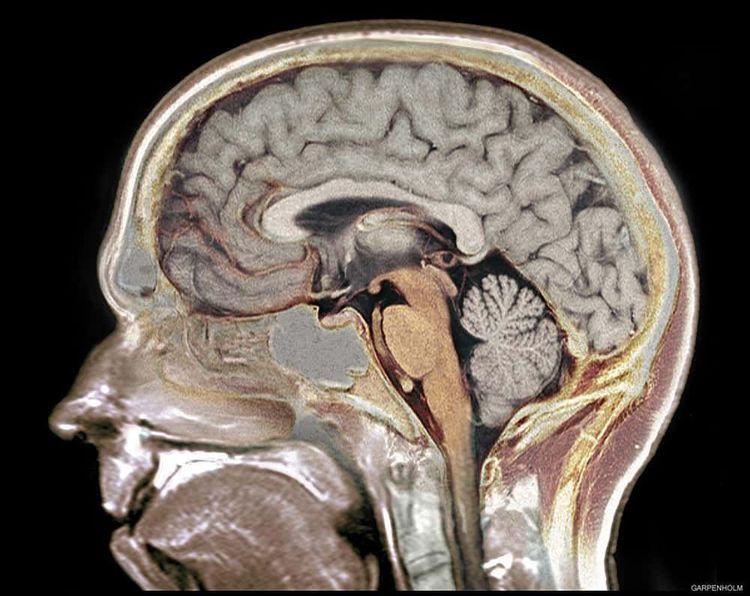

Финеас Гейдж умер в возрасте 36 лет. Его история стала одним из первых доказательств того, что разные участки мозга отвечают за личность и поведение человека. Череп Гейджа до сих пор хранится в Анатомическом музее Уоррена при Гарвардском университете.

3. Некоторые люди прожили почти обычную жизнь, практически не имея мозга

Мозг принято считать главным органом человеческого тела, без которого невозможно нормальное существование. Однако в медицинской практике зафиксированы случаи, которые ставят это убеждение под сомнение.

Один из самых поразительных примеров — история 44-летнего француза, обратившегося к врачам с жалобами на слабость в ноге. Обследование показало, что большая часть его мозга была замещена жидкостью из-за хронического нарушения оттока спинномозговой жидкости. Фактически у него оставалось около 10% мозговой ткани.

При этом мужчина был женат, воспитывал двоих детей и имел IQ около 75, что не считается тяжёлым интеллектуальным нарушением. Подобные случаи фиксировались и в других странах: например, у женщины из Китая полностью отсутствовал мозжечок, а у другого пациента функционировал практически один лишь ствол мозга. Эти истории до сих пор вызывают удивление и пересмотр представлений о возможностях человеческого организма.